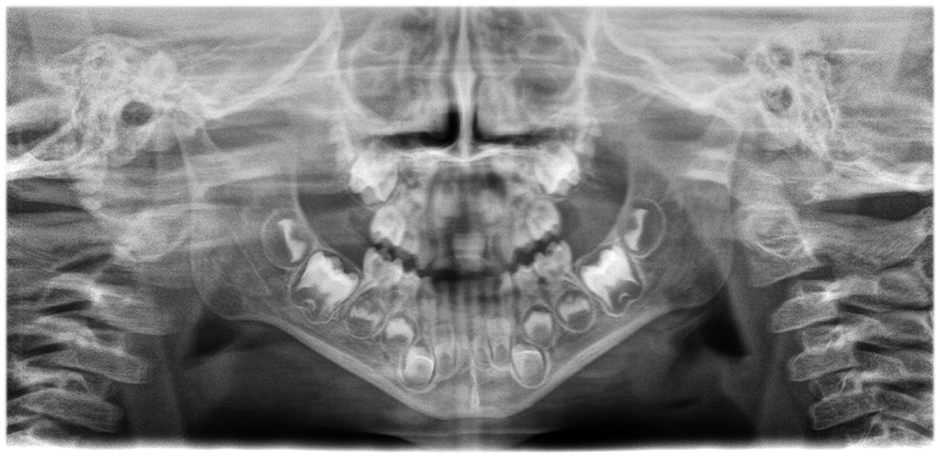

• Olağanüstü netlik ve çözünürlükte panorama görüntüler,

Hasta konumlandırma düzeltmesi ile sorunsuz bir şekilde entegre edilmiş yenilikçi 21 katmanlı otomatik odaklama sistemi.

Farkı görmek için kaydırıcıyı hareket ettirin (sol görüntü otomatik odaklama ve hasta konumlandırma düzeltmesi olmadan, sağ görüntü otomatik odaklama ve hasta konumlandırma düzeltmesi ile).